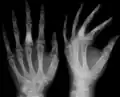

X-ray showing calcified enchondromas localized in finger a 37-year-old patient affected with Ollier disease -

The disease consists of the growth multiple enchondromas which usually develop in early childhood. The growth of these enchondromas usually stops after skeletal maturation.[4] The affected extremity is shortened (asymmetric dwarfism) and sometimes bowed due to epiphyseal fusion anomalies. Bone lesions generally present as cellular during childhood and become more solitary over time. People with Ollier disease are prone to breaking bones (fractures) and normally have swollen, aching limbs. However, many cases of solitary enchondromata go unnoticed due to lack of symptoms. Enchondromas are commonly found in the phalanges, metacarpal, and metatarsal bones in patients of Ollier disease due to the affinity of enchondromas to long tubular bones such as the femur and humerus. A unilateral distribution of bone lesions is usually observed but bilateral distributions or a singular extremity can occur as well. Approximately a third of the cases show some form of physical deformities of bowing or abnormal limb lengthening.